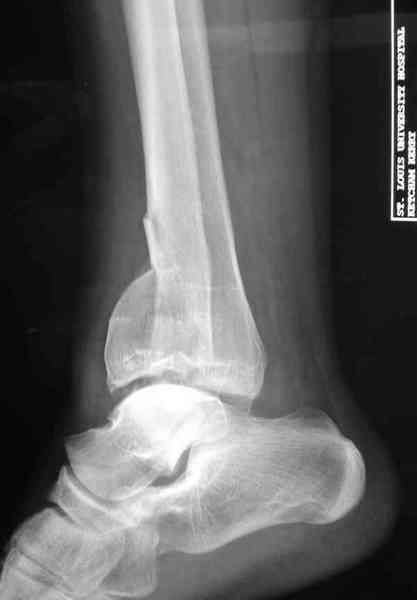

Яков изложил все необходимые аспекты лечения переломов пилона, и, не желая менять тему, решил выставить нашу точку зрения в двух клинических примерах.

При лечении внутрисуставных переломов типа "Pilon"

или "Tibial Plateau" на голени, применение простых

наружных фиксаторов типа "Spanning ExFix" или "Travelling ExFix" стал одним из стандартом этапного лечения.

Здесь выставлена пара случаев перелома пилона, оба

случая леченные этапным наружным фиксатором.

Второй случай фиксирован аппаратом Илизарова.